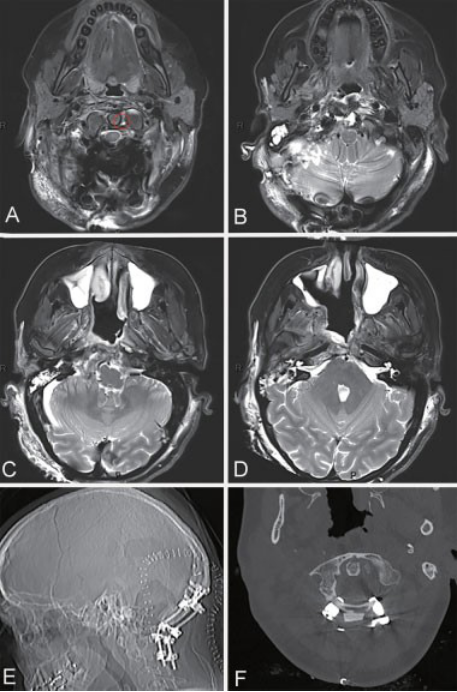

内镜鼻腔内肿瘤切除术后的影像学(一阶段)

在一开始干预后1个月,Sebastien Froelich教授为患者进行了右乙状窦后开颅联合FLA切开术,以接近右枕骨con,同侧椎动脉,牙周间隙并进入脊索瘤的硬膜内延伸区。术后MRI显示,对侧C1椎弓根仅可见少量脊索瘤残留,对肿瘤进行了全切切除。肿瘤切除后,Sebastien Froelich教授为患者进行了进行C0-C1-C2的后路固定。手在接下来的几个月中进行了辅助光子放射疗法(总计70.2 Gy)。自手术以来的两年随访中,没有肿瘤进展的迹象。

通过远侧入路进行二阶段开颅手术后的术后影像